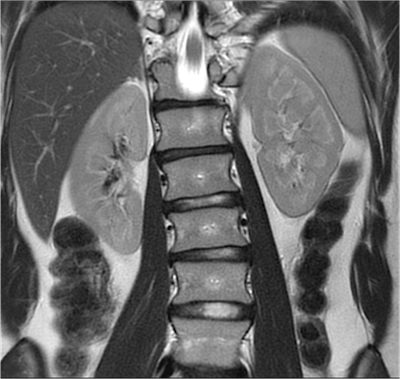

Abdominal MR scan taken on the 1.5-tesla Altea system using Caipirinha, a parallel imaging acquisition technique. Image courtesy of Siemens Healthineers."With rising patient volumes in the face of falling reimbursement, there is a clear need for greater efficiency and productivity. At the same time, the quality of exam results should not diminish," said Jan Chudzik, head of global product marketing for MRI at Siemens Healthineers, noting that there was a 20% reimbursement cut in Switzerland for imaging from 1 January 2018 and a 30% drop in reimbursement for neuro MRI over the past five years in the U.S., for example.